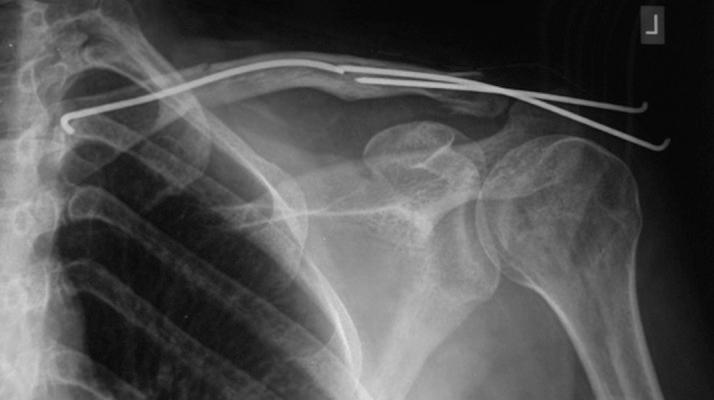

One of the modern techniques for the treatment of clavicle fracture (Fx) is elastic titanium intramedullary nailing. But, there are different opinions about this technique. We studied this technique in 12 patients with clavicle Fx and assessed its outcome.

We operated on 13 clavicle Fx in 12 patients from 2008 through 2012. We used a new technique called minimally invasive titanium elastic intramedullary nailing for operating patients with midshaft clavicular Fx.

Clinical union was achieved 3-5 weeks after the operation with no pain over Fx sites upon physical examination. Radiologic union appeared at 6 to 12 weeks .We did not encounter nonunion or infection, but one of the comminuted Fx united 1 cm shorter; however, it had a solid union with a good score. All but two patients had good scores.

Although controversy exist regarding intramedullary nailing of clavicle Fx, our results using this technique for minimally comminuted midshaft clavicular Fx were very good.